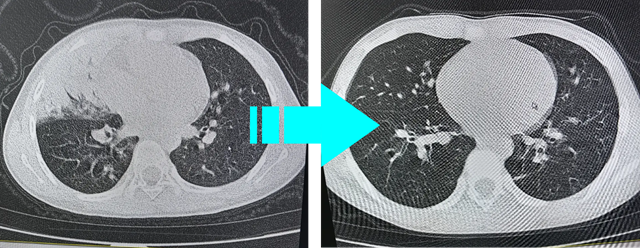

支原体肺炎,在这个冬天刷爆了存在感,很多小朋友一到医院检查,就发现肺部已经出现大面积“肺实变”“肺不张”等并发症,泸州小学生小西(化名)就刚刚经历了一次这样的惊险。她的右肺竟然大部分“失踪”了?

上面这段诊断,用通俗的话来讲就是在CT影像下小西的右中肺由于感染变得一片白茫茫,也就是家长们常说的“白肺了”。

罪魁祸首病原发现是“耐药的支原体”术后医生及时调整抗感染用药(点击查看往期科普)用药科普丨治疗肺炎支原体“新秀”——多西环素,经过不到2周的综合治疗小西体温稳定,咳嗽症状大部分消失,体力活动不受限,肺功能检查正常。

右肺找到啦!